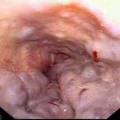

Варикозное кровотечение - это кровотечение из варикозно-расширенных вен пищевода или желудка при эндоскопическом обследовании или наличие крупных варикозных вен и крови в желудке, при отсутствии других причин кровотечения. Варикозное расширение вен пищевода является осложнением портальной гипертензии (повышение давления в воротной вене) и иногда является первым ее симптомом, например, у пациентов с циррозом на фоне гепатита С.

Классификация варикозно-расширенных вен (ВРВ) пищевода: расширение вен до 3 мм соответствует 1й степени ВРВ, 3–5 мм – 2й степени, 5 мм и более –3й степени ВРВ.